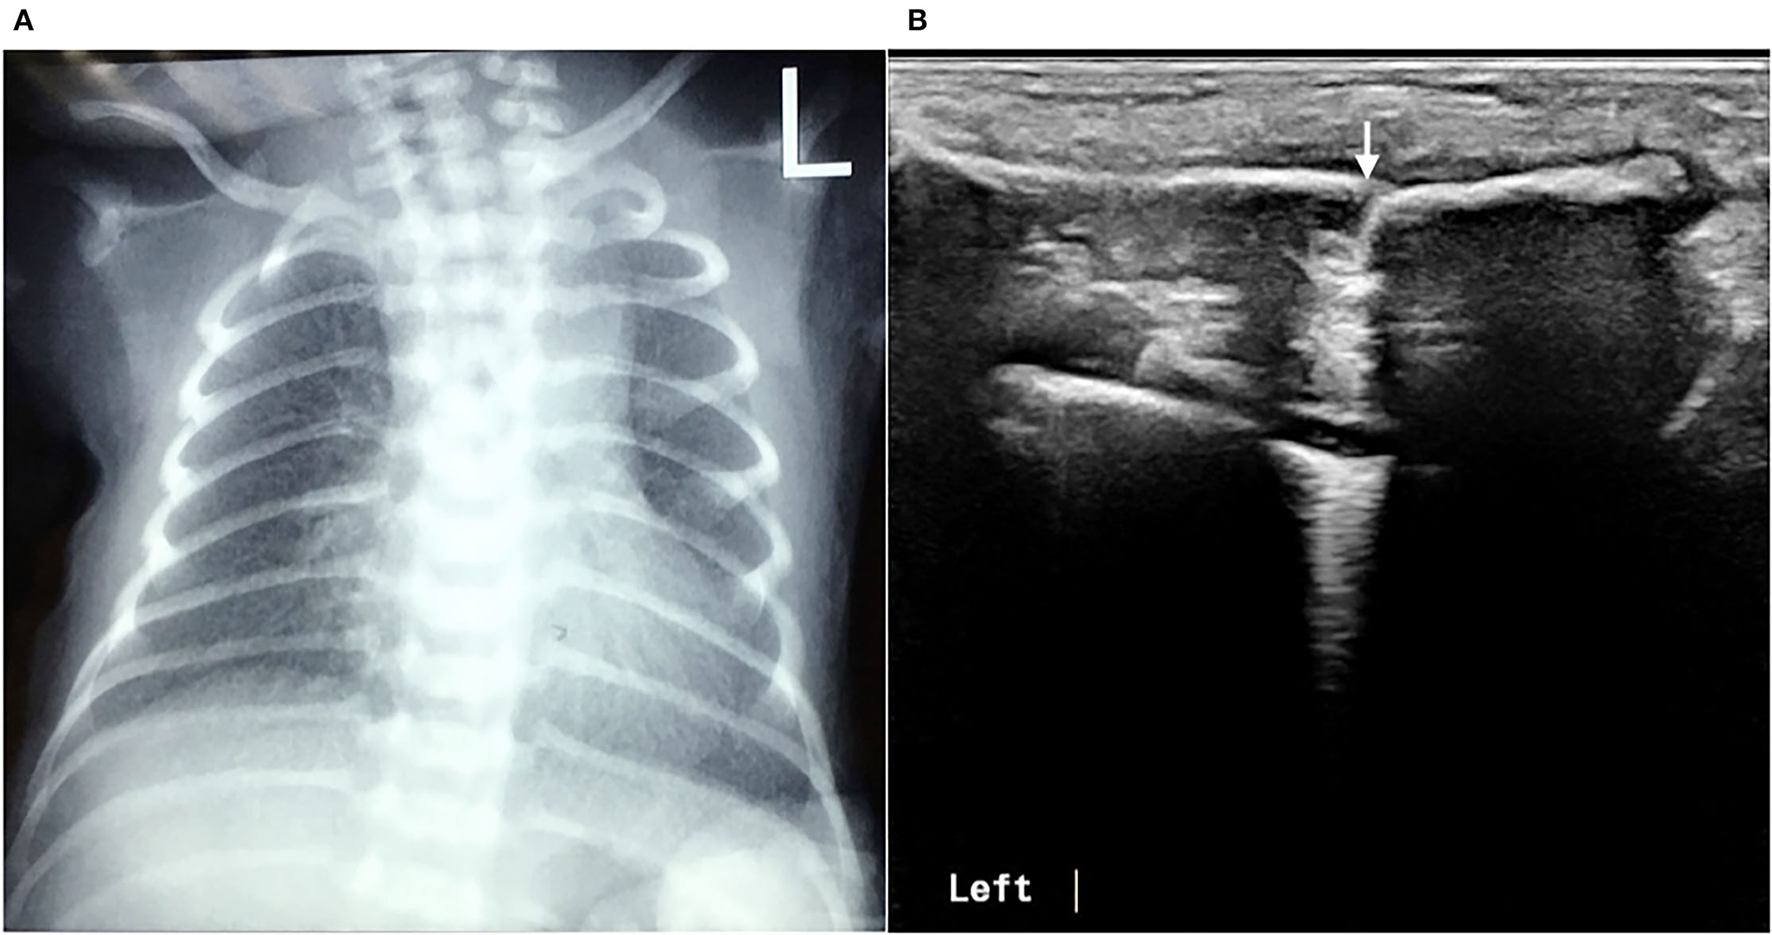

In this study, 30 infants with clavicle fractures underwent both X-ray and ultrasound examinations. The results showed that all 30 fractures were detected by ultrasound, but one fracture was not detected by X-ray (Figure 8). Therefore, the sensitivity of ultrasound diagnosis of fractures (100%) is higher than that of X-ray (97.7%). The specificity of ultrasound for diagnosing clavicle fractures was 100%.

Figure 8

Missed clavicle fracture on X-ray. The infant underwent a chest X-ray due to postnatal dyspnea, but there were no signs of fractures in either clavicle (A). Physical examination found a bone rubbing sensation on the left clavicle on admission, and the subsequent ultrasound examination confirmed the presence of a fracture of the left clavicle (B).

Generally, the diagnosis of clavicular fractures mainly depends on chest X-ray examination, which can detect fracture lines. X-ray is considered the “gold standard” for fracture diagnosis. The results of this study showed that using ultrasound to diagnose fractures is more accurate and reliable than a chest X-ray. Ultrasound detected 100% of neonatal fractures, and both its sensitivity and specificity for the diagnosis of fractures were 100%. In contrast, X-ray missed one case of clavicle fracture, so its positive rate for the diagnosis of fracture was only 96.7%. With ultrasound, the scanning direction and angle can be adjusted at any time as needed and according to the position of the infant, while X-ray does not allow for adjustments. X-ray can lead to missed diagnosis of fractures (especially clavicle fractures) due to the influence of factors, such as the body position of the infant, the position of the bone at the time of imaging, the angle of the imaging or X-ray, and the alignment of the broken ends of the fracture (when the broken ends of fractures are well aligned, X-ray examinations often fail to detect them). Therefore, ultrasound is superior to X-ray for the diagnosis of neonatal fractures. The superiority of ultrasound is especially obvious for the diagnosis of neonatal rib fractures, and it can identify fractures that X-ray cannot detect (10, 11). Among the 52 patients, there were 46 cases of clavicle fracture, 3 cases of skull fracture, 2 cases of rib fracture, and 1 case of humerus fracture, and all fractures were clearly diagnosed by ultrasound. This indicates that ultrasound can not only accurately diagnose the most common clavicle fractures in clinical practice, but can also accurately diagnose relatively rare rib fractures, limb fractures, and skull fractures. In addition, X-ray is inconvenient and time-consuming, increasing radiation exposure not only to the patient himself but also to other infants within the same wards and medical staff. Therefore, the use of ultrasound for the diagnosis of neonatal fractures is of great value.